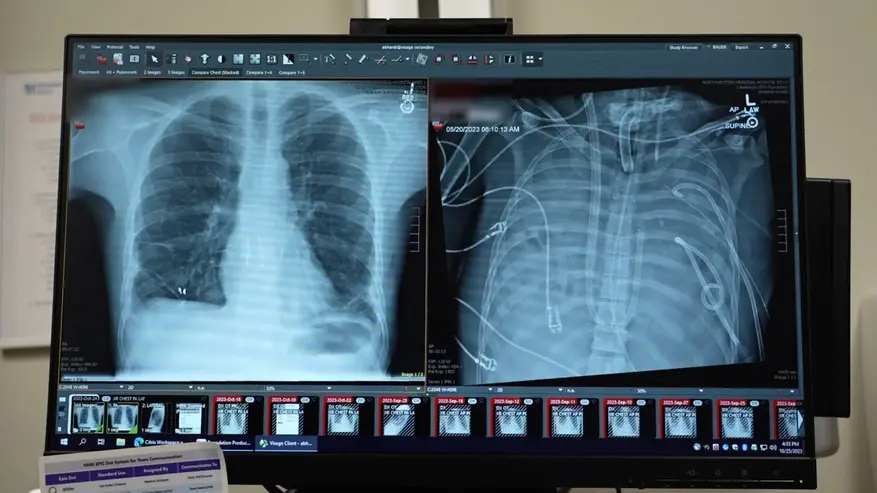

Согласно отчету хирургов из Северо-Западного университета (Northwestern University), опубликованному в журнале Med, зафиксирован уникальный случай выживания пациента после полного удаления обоих легких. Сообщается, что 33-летний мужчина провел 48 часов без органов дыхания, пока врачи боролись с тяжелейшей инфекцией, вызванной осложнениями после гриппа. По словам медиков, легкие пациента были настолько повреждены воспалением и бактериальной пневмонией, что стали источником заражения для всего организма.

Как поясняют авторы работы, единственным шансом на спасение пациента являлась двусторонняя трансплантация легких, однако тяжелое состояние не позволяло провести операцию незамедлительно. Медики приняли решение полностью удалить пораженные некрозом ткани, чтобы купировать дальнейшее распространение инфекции. На период отсутствия органов дыхание обеспечивала специальная система экстракорпоральной мембранной оксигенации («искусственное легкое»), которая насыщала кровь кислородом и удаляла углекислый газ, одновременно поддерживая работу сердца и почек.

Руководитель исследования Анкит Бхарат (Ankit Bharat) заявляет, что этот случай дает биологическое доказательство необратимости повреждений при тяжелом респираторном дистресс-синдроме. Спустя два дня после удаления легких были найдены донорские органы, и хирурги успешно провели пересадку. Сообщается, что спустя два года после операции пациент вернулся к нормальной жизни. По версии ученых, подобный подход может стать «мостом» к трансплантации для критически больных пациентов, которые ранее считались безнадежными.